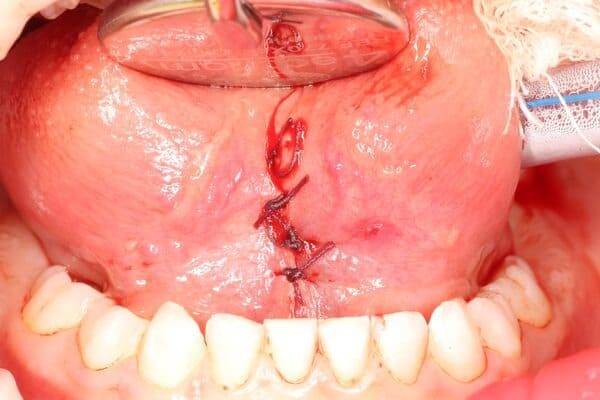

Дівчинка 7 років, перше вересня, гойдалка… Вивих постійного зуба: якщо в такій ситуації зволікати, дитина може втрати постійний зуб назавжди. Батькам порекомендували нас і пацієнти одразу приїхали. Через складність і травматичність процедур вирішено проводити лікування в анестезіологічному супроводі. Зуб поставлений на місце (репонований), проведена хірургічна обробка і ушивання рани губи. Останнє фото через рік після травми: зуб на місці і корінь продовжує розвиватись, губа повністю загоїлась